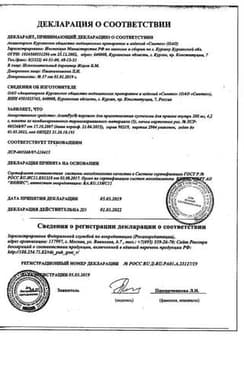

Сертификаты